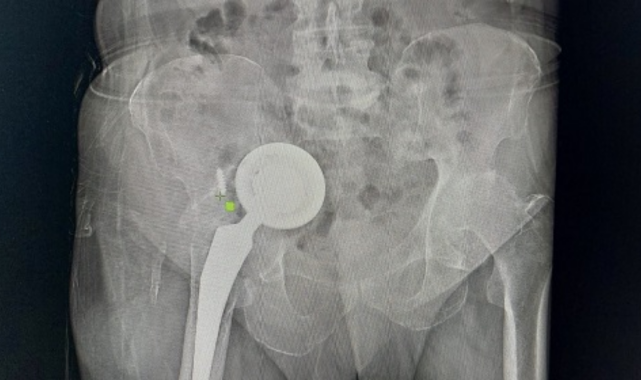

Adıyaman’da yaşayan 74 yaşındaki Ömer Demir, geçtiğimiz yıllarda kalça bölgesinde hissettiği rahatsızlıklar sonrası doktora gitti. Kalçasında kireçlenme olduğu belirlenen Demir, kalça protezi ameliyatıyla şikayetlerinden kurtuldu. Edinilen bilgiye göre zaman içerisinde yeniden ağrılar hissederek hastaneye başvuran Demir’in protezine revizyon ameliyatı yapıldı. Ancak bir süre sonra yaşlı adamın ağrıları yeniden kendini gösterdi ve uzmanlar operasyon gerekliliğini ifade etti. İddiaya göre geçirdiği operasyonlar sonrası tekrar ameliyat olmak istemeyen Demir, gittiği birçok doktoru dinlemedi, protezi ise karın içi ve uyluk kemiğinde ilerlemeye başladı. Zamanla ağrıları dayanılmaz hale gelen yaşlı adam, en son Başakşehir Çam ve Sakura Şehir Hastanesi’ne geldi. Burada yapılan tetkikler sonrası protezin diğer organlarını olumsuz etkileyecek şekilde vücudunda ilerlediğini duyan yaşlı adam, ameliyata onay verince acil şekilde operasyona alındı. Başakşehir Çam ve Sakura Şehir Hastanesi Ortopedi ve Travmatoloji Uzmanları Dr. Mustafa Özçamdallı ve Dr. Necati Doğan’ın ekipleriyle gerçekleştirdiği operasyonla protezin üst kısmı karın içinden alt kısmı ise hastanın bacağından çıkarıldı. Yeni protez ise başarılı bir şekilde bölgeye yerleştirildi. Hastada yaşanan durumla çok sık karşılaşmadıklarını ifade eden Uzm. Dr. Özçamdallı ve Doğan tedaviye ilişkin bilgi verirken Demir, yaşadıklarını anlattı.

Demir'in geldiği pozisyonu ve uyguladıkları tedaviyi anlatan Dr. Necati Doğan, “Hastamıza yıllar önce kalça kireçlenmesi nedeniyle kalça protezi uygulanmış, bu protez uygulamalarında sıklıkla başarılı sonuçlar elde ederiz. Daha önce gittiği hastanelerde bu protezin yenilenmesi gerektiğini hastamıza söylemişler. Hastamız o anki risklerden dolayı bu süreci kabul etmemiş, ötelemiş ve yaklaşık 2-3 yıl boyunca bu protezi kullanmaya devam etmiş. Protezde ilerlemeye devam etmiş. Bize başvurduğunda artık protez karın içindeki organların arasına kadar yerleşmişti. Bacakta ciddi şişlikleri, hareket kısıtlılıkları oluşmuş, yürüyemez hale gelmişti. Yenileme ameliyatı gerektiğini söyledik ve hastamız artık mevcut tablosundan ileri derecede şikayetçi olduğu için belirli riskleri, ameliyatı kabul etti. Protezin bu kadar ileriye gitme aşaması sık karşılaştığımız bir şey değil, daha erken evrelerde geldiklerinde sadece kalça bölgesi açılır. Daha uyumlu protezlerle kalçadaki implant değiştirilir ve hayatına geri döner. Ama bu hastamız artık normal bölgeden çıkarılamayacak derecede ilerlemiş formuyla geldiği için bizim bu protezi kalça bölgesinden çıkarıp onarmamız imkansızdı. İlk olarak karın içindeki kısımları çıkartmak için karın bölgesinden girdik. Protezin yuva baş dediğimiz kısımlarını karın içinde mesanenin, bağırsakların, damar sinir paketlerinin arasından güvenli ve sorunsuz bir şekilde çıkarttık. Daha sonra bu kemikte oluşmuş ileri derecedeki defekti de onarmak gerekiyordu, buraya da uygun platinlerle tekrardan yeni yapılan protezler içeri gelmesin diye yeni platinlerle bir destek kısmı oluşturduk. Karın iç kısmındaki işimiz bitti daha sonra ikinci bir aşamada kalça bölgesinde kalan kısmı çıkarttık. Şu anki protezimiz gayet stabil ve hemen hareket etmeye, yük vermeye, yürümeye uygun bir protez. Vatandaşların protezlerini düzenli takip ettirmeleri gelişen herhangi bir yeni şiddetli ağrı ve problemlerde mutlaka en erken dönemde bu aşamalara gelmeden kontrollerini yaptırmalarını öneririm" dedi.

Protezin üst kısmının karın içinden alt kısmının ise bacaktan çıkarıldığını ifade eden Ortopedi ve Travmatoloji Uzmanı Dr. Mustafa Özçamdallı, “Hastamız bize geldiğinde yürüyemez bir vaziyetteydi daha önce birkaç kez operasyon geçirmiş ve protezi karın dediğimiz boşluğa kadar ulaşmış durumdaydı. Hastanın damarlarında ve sinirlerinde hasarlar meydana getirebilecek seviyedeydi. Özel dizayn edilmiş kafes dediğimiz protezlerle ve daha uzun revizyon dediğimiz protezlerle hastamızın operasyonunu başarılı şekilde gerçekleştirdik. Böyle durumlar hastaların ilerleyen dönemlerinde dolaşımını bozup bacaklarımı kaybetmeye kadar gidebilir. Bu hastamızda ek birtakım rahatsızlıklar olması sebebiyle diyabet, kalp rahatsızlığı, sebebiyle yatağa bağımlı olması bu hastalarda mortalite dediğimiz durumu arttırmaktadır. Bu çok sık karşılaştığımız bir hasta grubu değil. Kesinlikle kalça protezi yapılan hastalarımızın kontrollerine rutin olarak gitmeleri gerekir. Bu hastamız biraz operasyonlardan çekinmiş ve birkaç operasyona girince, çok yüksek olduğu anlatılınca korkmuş ve dolayısıyla bu şekilde hayatını bir 3-4 yıl daha idame ettirince protezin daha da aşınıp leğen kemiğinin yukarısına doğru çıkmasına sebep olmuş. Kendisine ameliyat önerilmesine rağmen ameliyatlarını kabul etmemişti ve bu protez leğen kemiğinde aşınmaya sebep olup karın içi organlara kadar ilerlemiş vaziyetteydi. Biz protezi 2 parça halinde çıkarttık. Protezin üst kısmını karın bölgesinden, alt kısmını uyluk kemiğinden çıkarttık" diye konuştu.